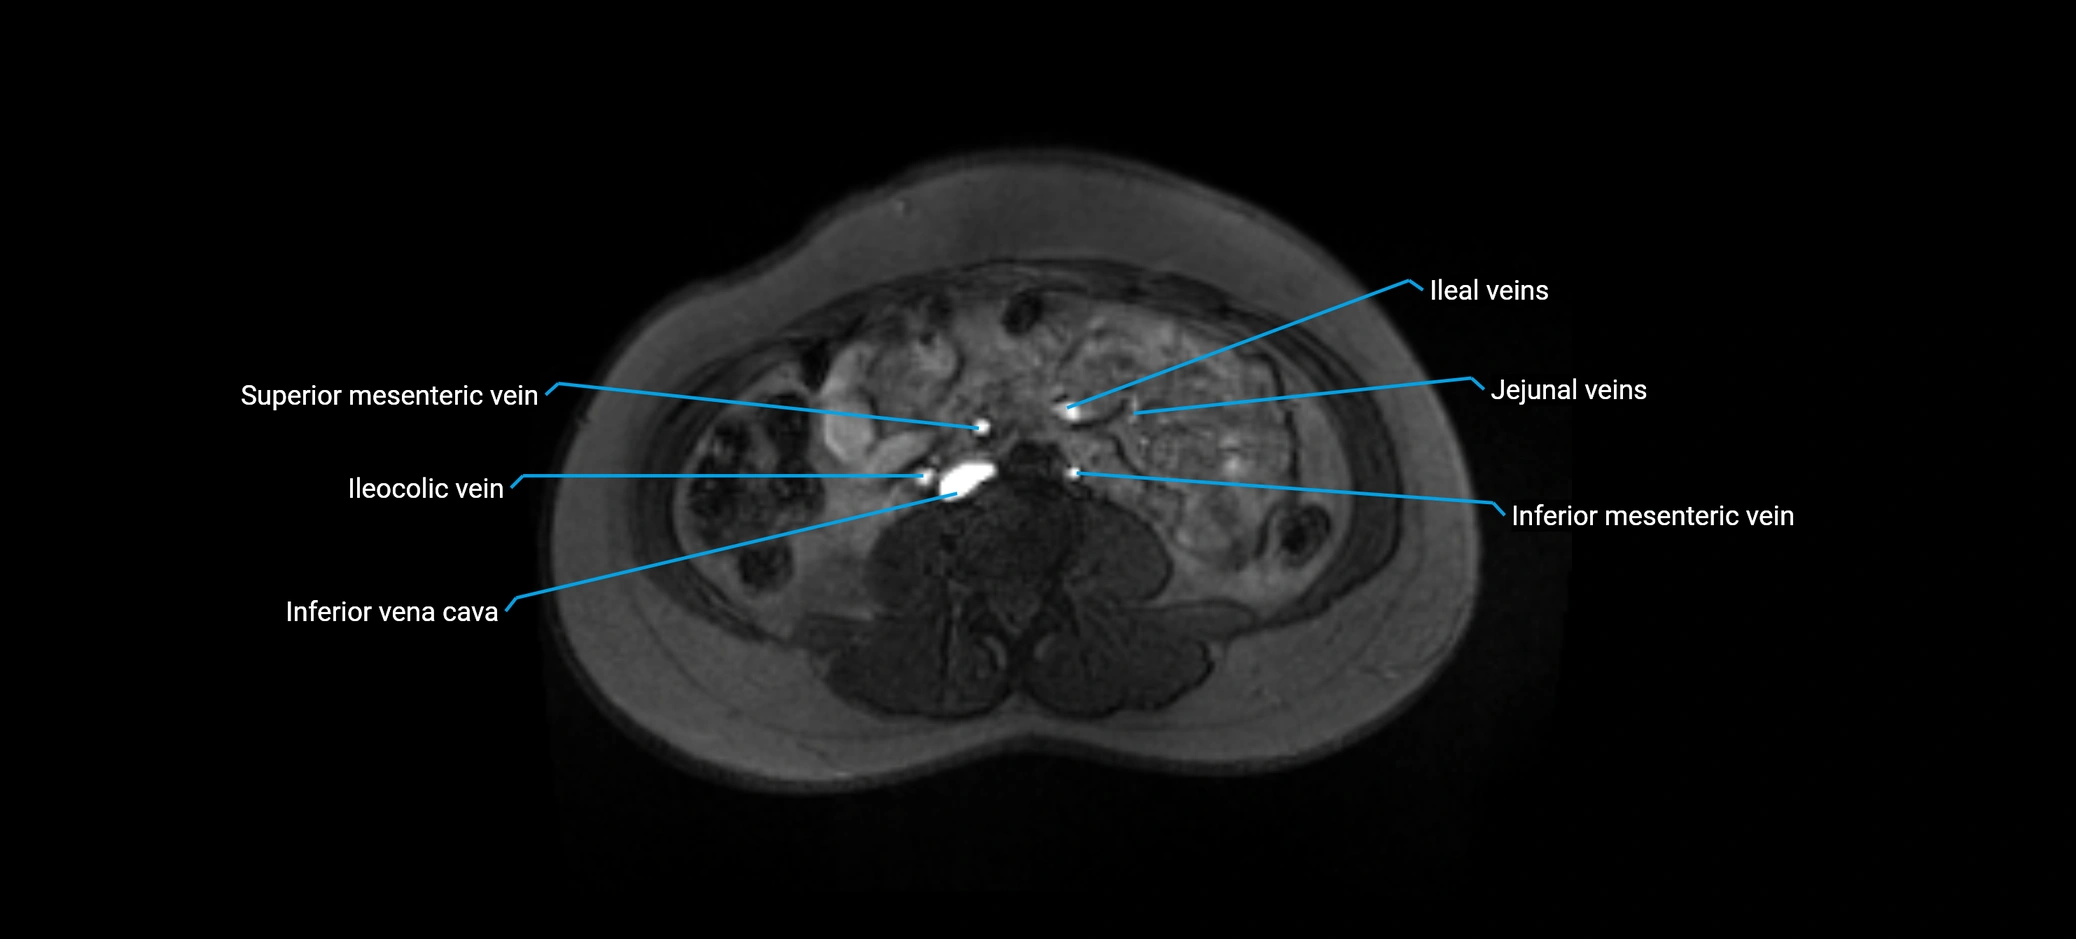

MRV TOF (Time-of-Flight MR Venography):

• Appears as a bright, high-signal vascular channel representing flowing blood

• Clearly shows branching pattern of right portal vein into anterior and posterior branches

• Best in coronal or axial reconstructions for segmental mapping

• No need for contrast, relies on flow-related enhancement

MRI image

image